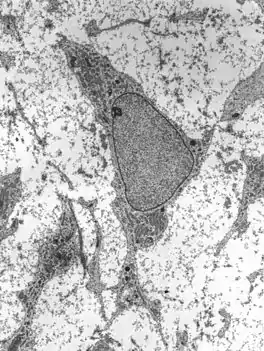

Mesenchymal stem cells within mesenchyme or the medullary cavity of a bone fracture initiate the process of intramembranous ossification. A mesenchymal stem cell, or MSC, is an unspecialized cell that can develop into an osteoblast. Before it begins to develop, the morphological characteristics of a MSC are: A small cell body with a few cell processes that are long and thin; a large, round nucleus with a prominent nucleolus that is surrounded by finely dispersed chromatin particles, giving the nucleus a clear appearance; and a small amount of Golgi apparatus, rough endoplasmic reticulum, mitochondria, and polyribosomes. Furthermore, the mesenchymal stem cells are widely dispersed within an extracellular matrix that is devoid of every type of collagen, except for a few reticular fibrils.[1]